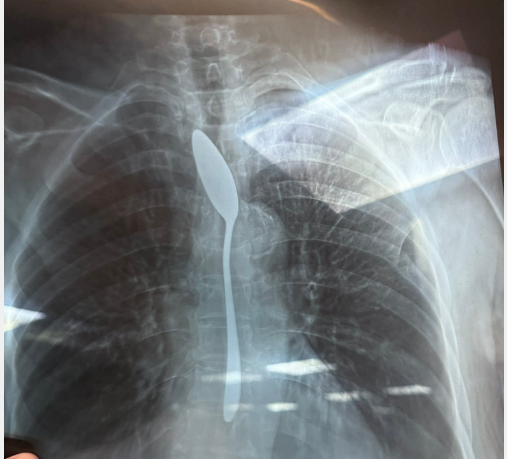

نجح فريق طبي بقسم الجراحة العامة في مستشفى شبين الكوم التعليمي بمحافظة المنوفية في إجراء عملية دقيقة لاستخراج ملعقة من بطن سيدة مسنة تبلغ من العمر 70 عامًا.

وأضاف أنه تم إجراء أشعة فورية للمريضة، والتي أكدت وجود جسم معدني داخل المعدة، وعلى الفور تم تجهيز الحالة ودخولها غرفة العمليات، حيث تمكن الفريق الطبي من استخراج الملعقة خلال مدة قياسية تراوحت بين 5 و7 دقائق فقط.